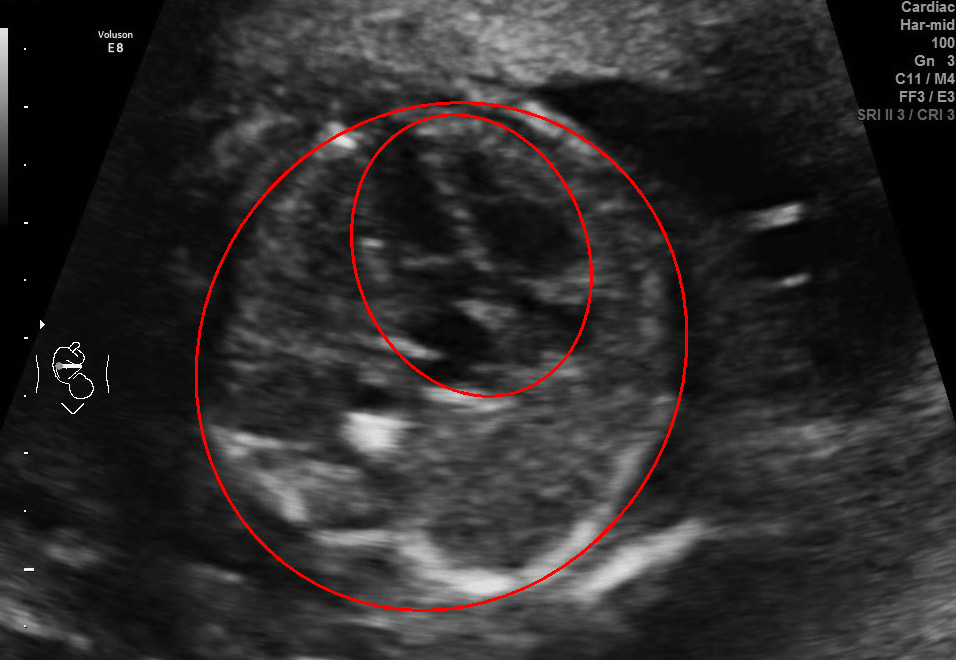

Visualization results of different methods.

Although the segmentation model trained on the fetal ultrasound dataset achieves a relative high average dice scores averaging over 0.9, the fitted ellipse highly depends on the segmentation results. As shown in the middle row of Fig. 2, the segment-based ellipse-fit method performs well when the image quality is good (first row), but the performance degrades when the segmentation is affected by image artifacts such as the acoustic shadowing (second and third row). Our proposed method is more robust to image quality and shadows. We also tried to compare to the GPN [9] with their open source code on our dataset, however, the results are not comparable to ours and those presented in Table. 1. It is difficult to conclude whether it is caused by the network itself or the training strategies. We, therefore, did not include the comparative results in this work.

As shown in Fig. 3 , both the proposed ellipse regression loss and IoU loss are necessary for ellipse detection. If the EllipseNet only supervised by IoU loss (first column), the model fails to optimize the major and minor axis separately, and the predicted ellipses degenerate into circles like the CircleNet. It is clear that the supervision of IoU loss can help to improve the prediction of location and shape (first and second row) and to correct the angle (last row).